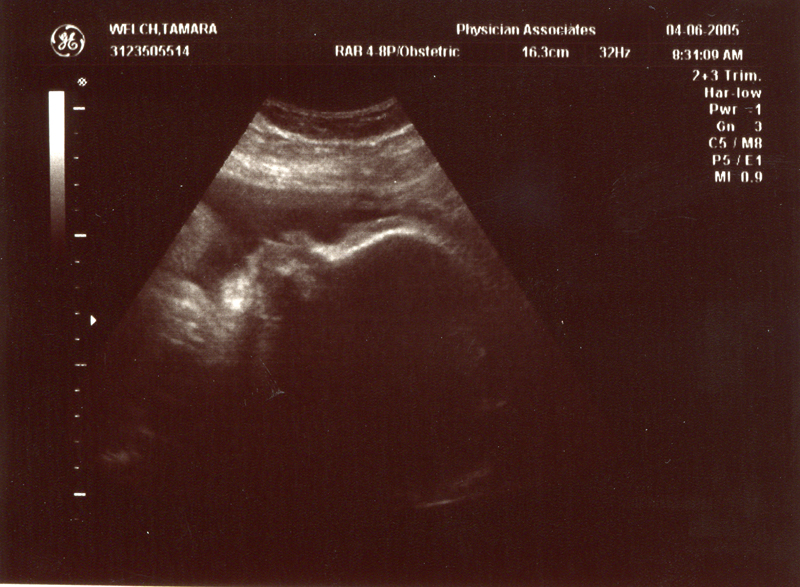

April 6, 2005 - Tammy went to the doctor and had a final ultrasound. All is well!